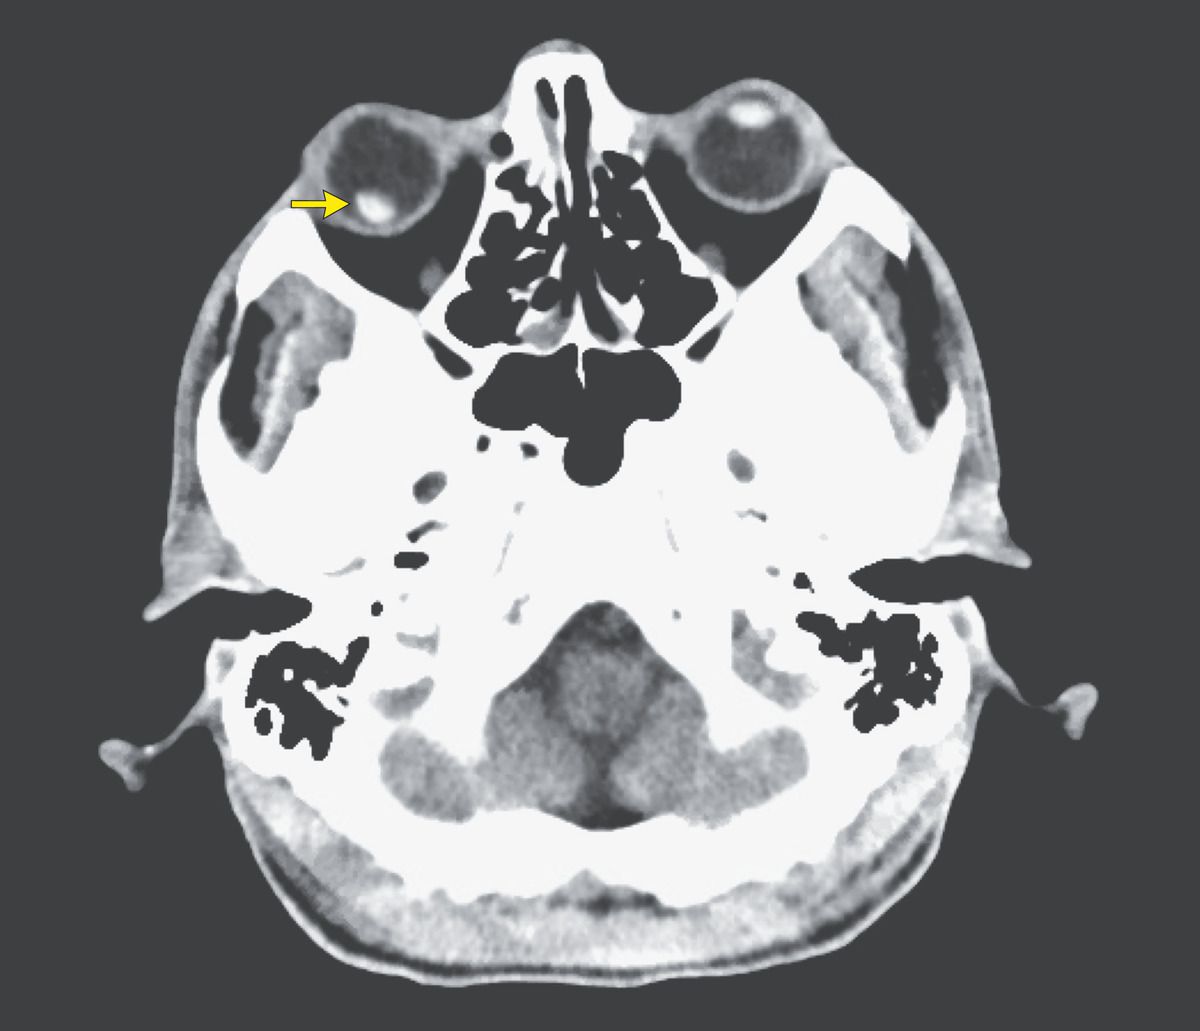

A 60-year-old man with alcohol and opioid use disorders presented to the emergency department with decreased vision in his right eye after falling down stairs 3 days earlier. On examination, there were abrasions on the right supraorbital area and forehead. The right eye was erythematous, and he reported pain with extraocular movement. The uncorrected vision in the left eye was 20/50, but using the right eye he was unable to count fingers and was able only to detect hand motion and light and to track a finger. A computed tomographic scan of the head and facial bones showed dislocation of the right intraocular lens (arrow). There were no facial bone or orbital wall fractures and no evidence of intracranial hemorrhage. The patient had no other trauma injuries for which intervention was indicated. He was transferred to a tertiary care center for definitive ophthalmologic treatment.